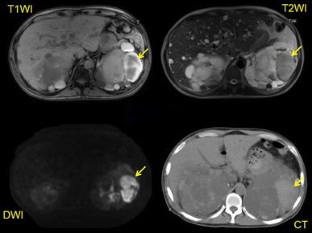

There were 24 patients with cyst infection (36 infected cysts) and 12 patients with acute cyst hemorrhage (13 bleeding cysts). White blood cell (WBC) count >10,000/μl, serum C-reactive protein (CRP) >15.0 mg/dl, and body temperature >38 °C strongly suggested cyst infection. All of the cysts with hemorrhage contained a high-density mass-like area or showed overall high density on CT, and all patients with cyst hemorrhage had abdominal pain or gross hematuria. On the other hand, infected cysts showed an increase of intensity on MRI [diffusion-weighted imaging (DWI)], while a fluid–fluid level, wall thickening, and gas were also evidence of infection. Abdominal pain and/or sequential changes on MRI after onset of symptoms were useful for localizing infected cysts.

Fig. 1